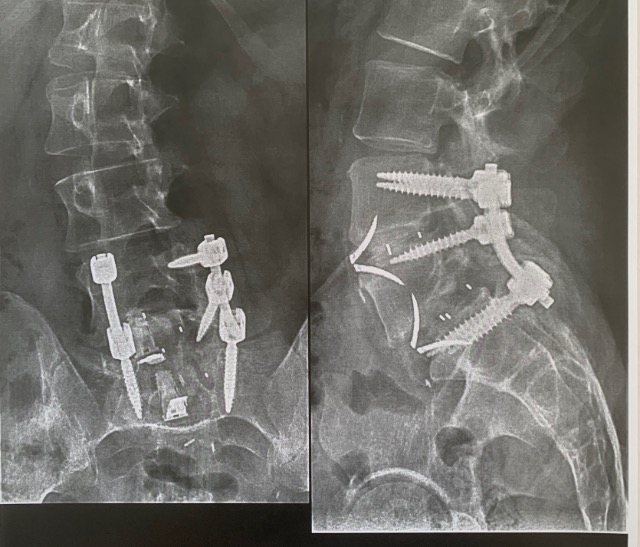

Benjiski Arthrodèse L4/L5/S1 les 10 et 18 octobre 2019 Page 3 Arthrodèse lombaire

Spondylolisthesis de L5 sur S1 de grade III (Glissement anterieur tres important du corps

spondylolisthesis par lyse isthmique bilaterale spondylolisthesis traitement espace francilien

spondylolisthesis par lyse isthmique bilaterale spondylolisthesis traitement espace francilien